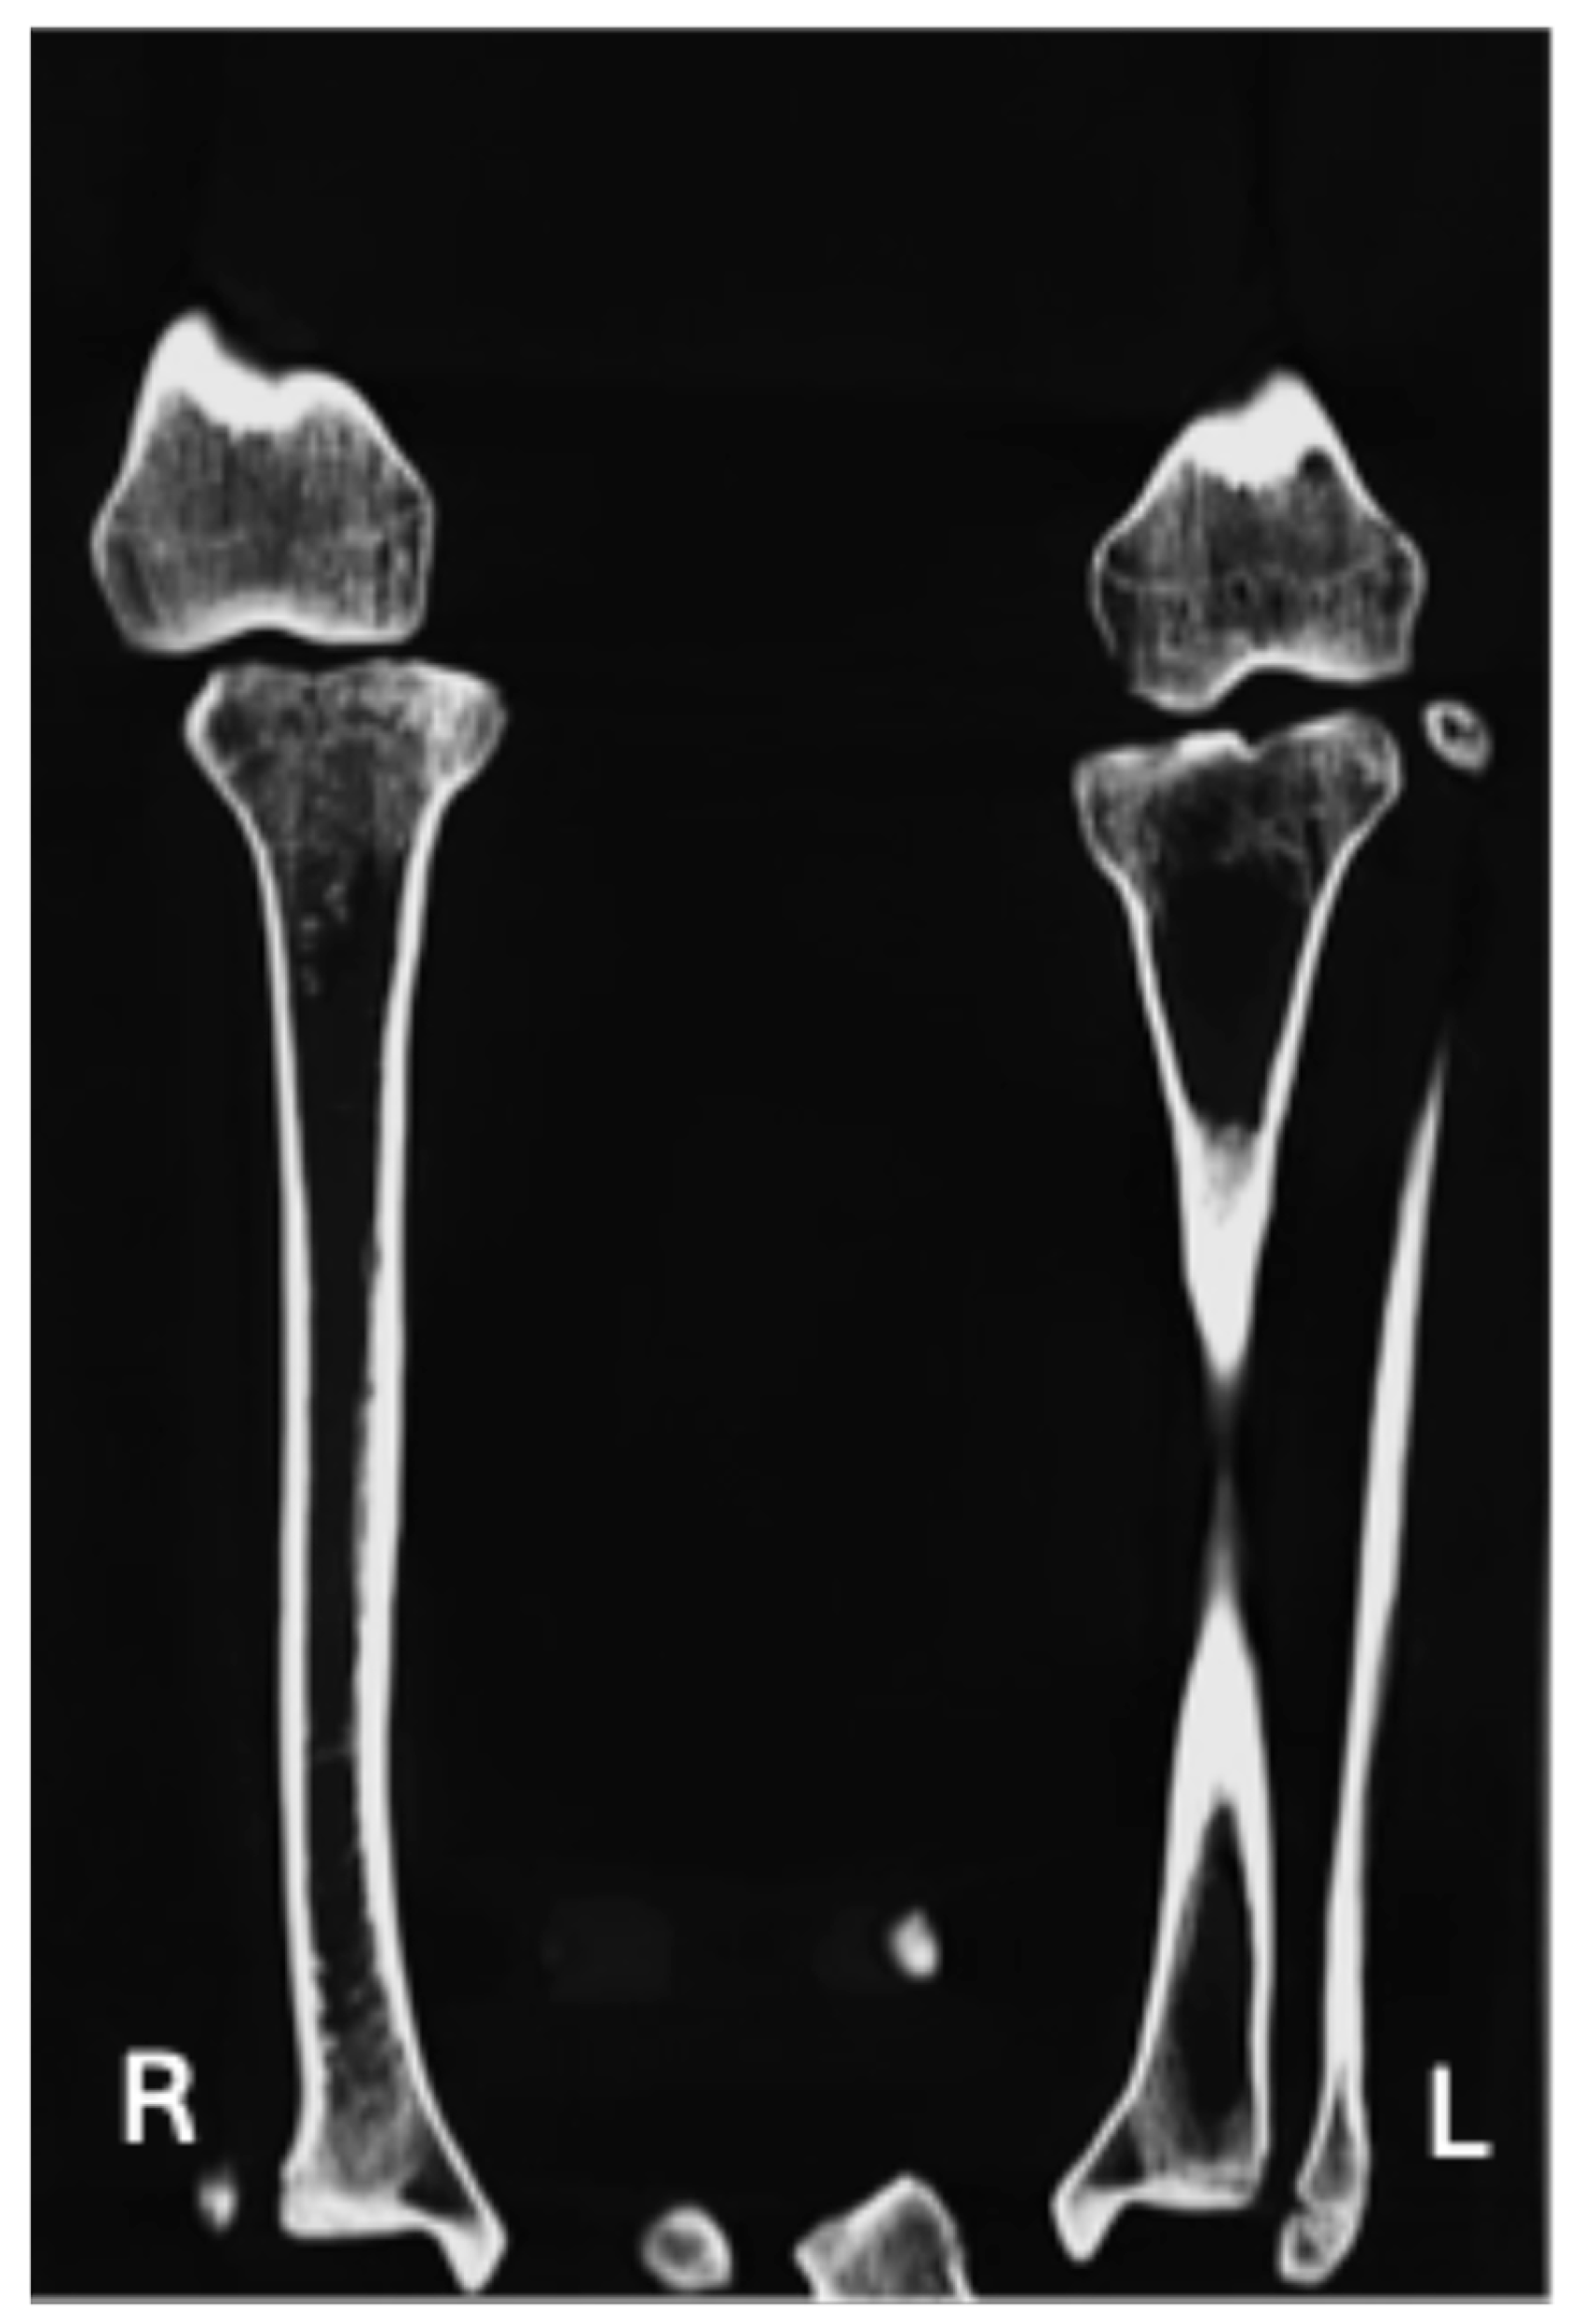

| Contralateral hip joint is definitively unaffected (Figure 4 and Figure 5) | X | X |

| Periarticular osteoporosis (Figure 4) | X | |

| Subchondral sclerosis (Figure 4) | X | |

| Lack of development of the intertrochanteric crest (Figure 2a and Figure 4) | X | X |

| Lack of development of the trochanteric fossa (Figure 2a and Figure 4) | X | X |

| Occult fractures (Figure 4) | X | |